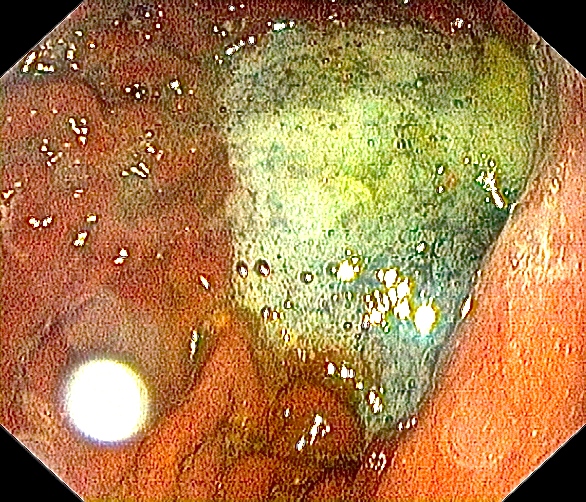

Mer spiserør.

Magesekk.